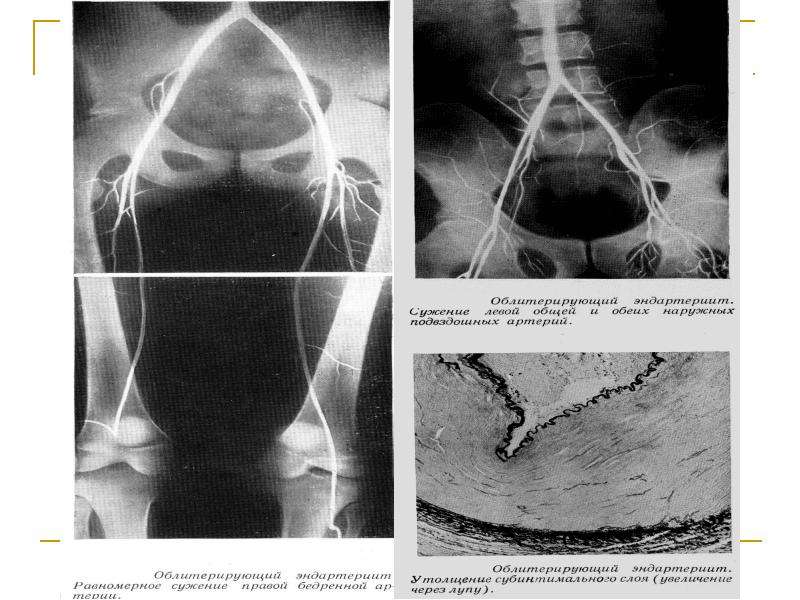

Изображения, связанные с атеросклерозом нижних конечностей и его лечением